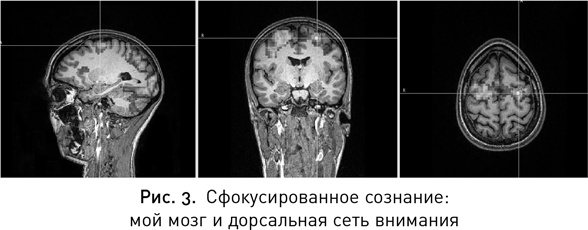

Мы направляемся в комнату с большим креслом — теперь в ней появился просто необъятных размеров монитор. Мой мозг (рис. 3). Не знаю, чего именно я ожидала, но выглядит он вполне нормально; все нужные бугры на месте, никаких дыр нигде нет. Майк перекрыл место расположения дорсальной сети внимания снимком моего мозга и отметил цель на зоне сети, которая называется фронтальным глазным полем, — сюда и будет нацелена стимуляция.